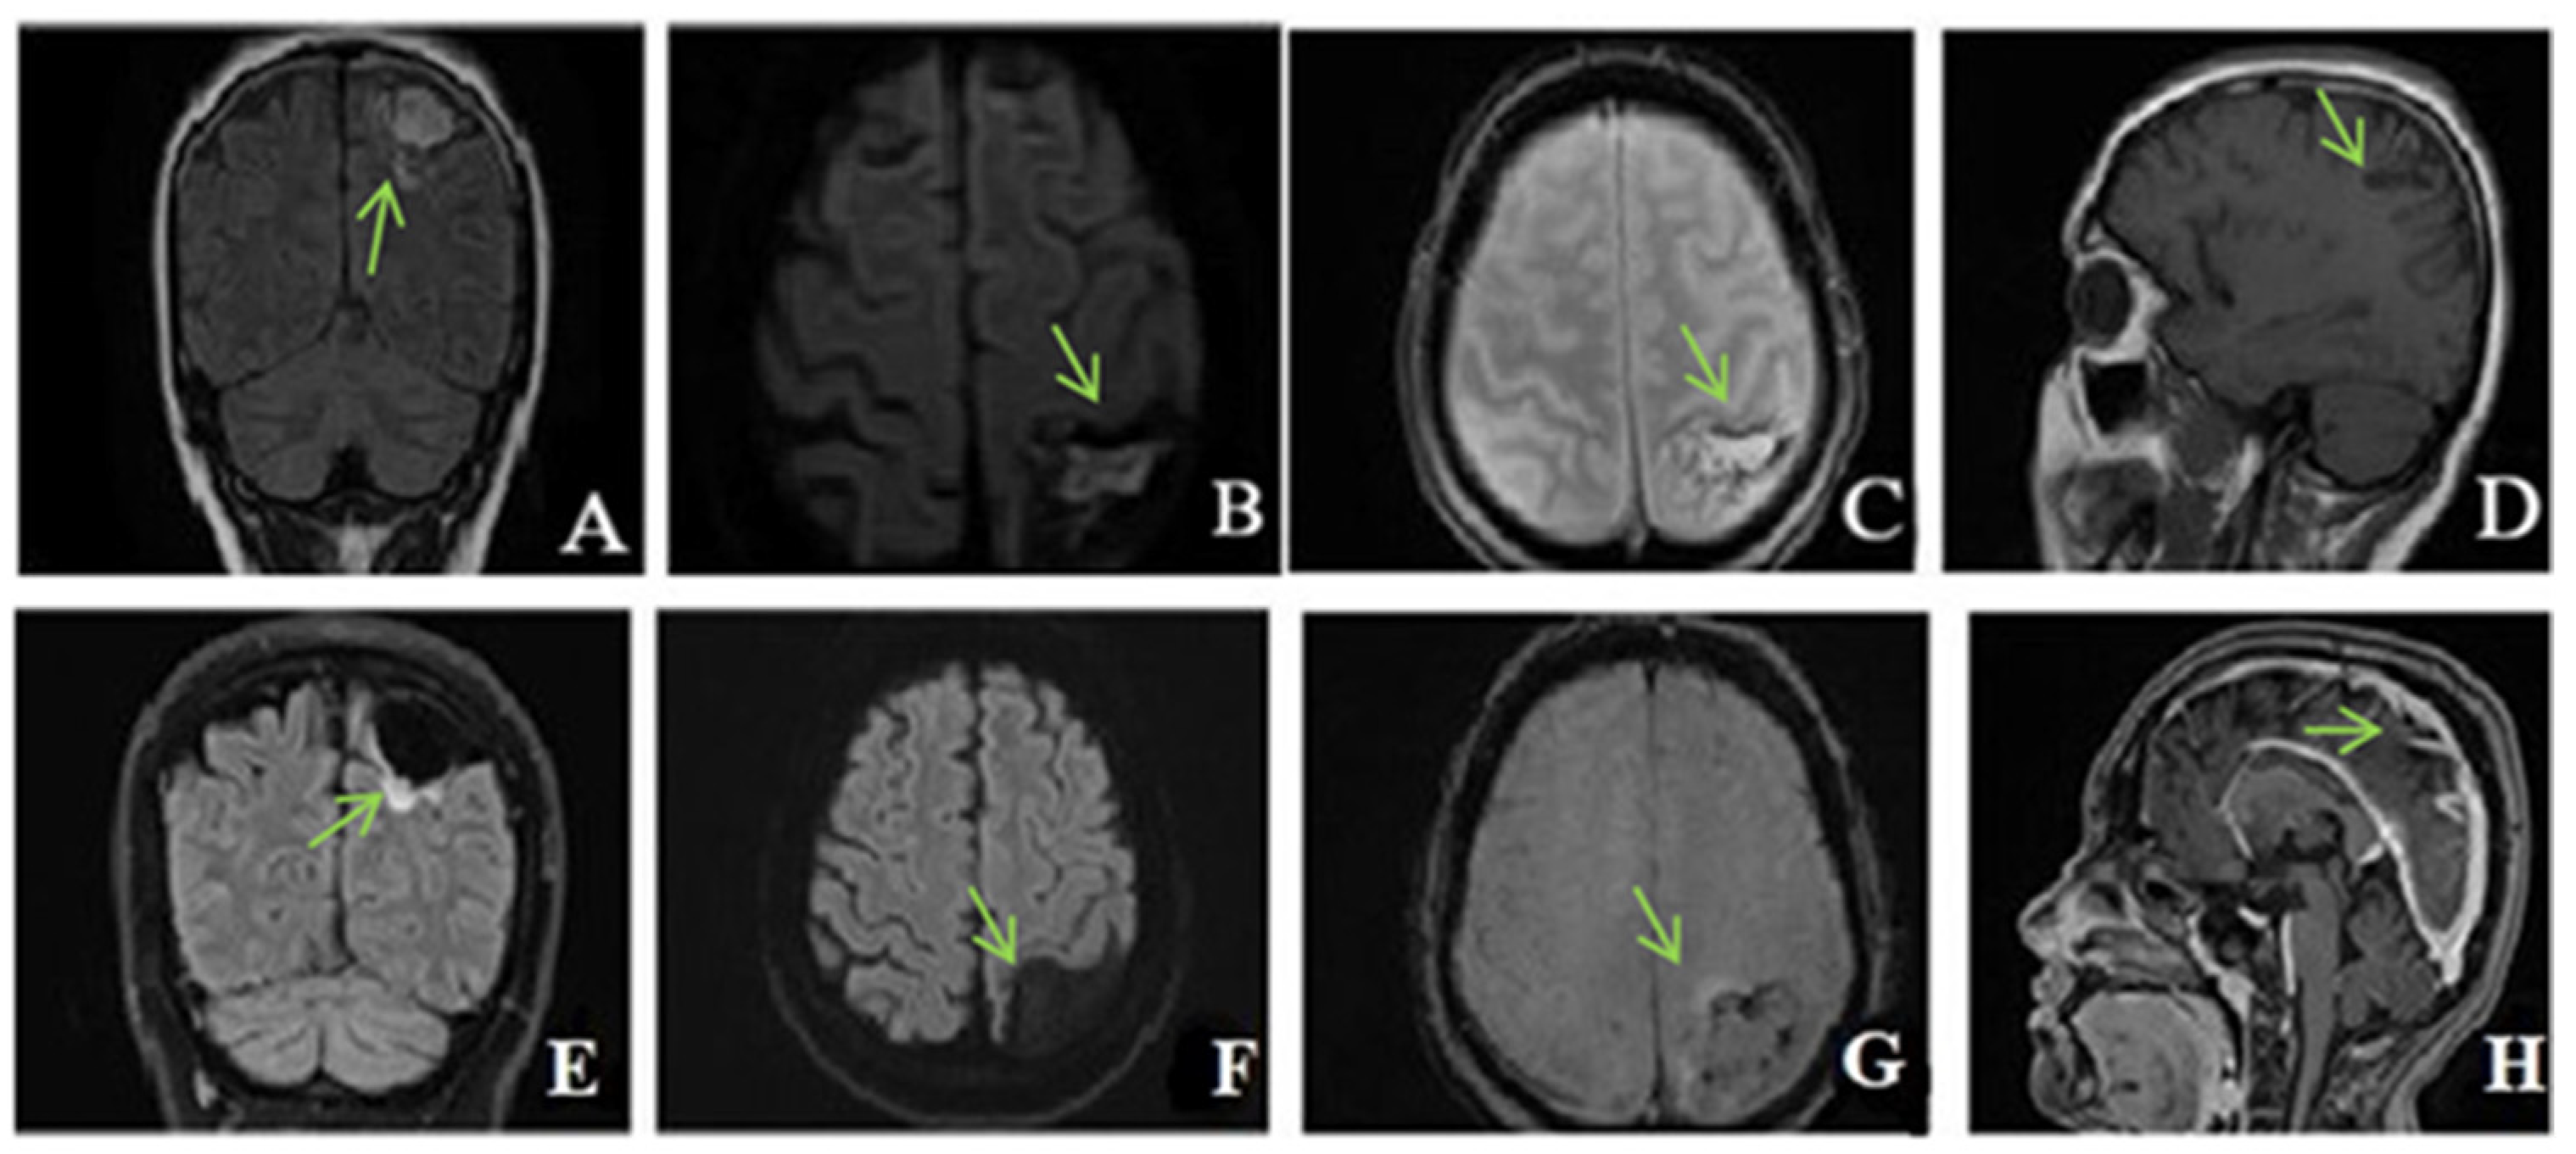

Native head CT performed at admission (Figure 4) showed increased dimensions of sinuses, and hyperdense content in the superior longitudinal sagittal sinus, the right sinus, and, contiguously, the inferior longitudinal sinus as well as in the right transverse sinus and partially the right sigmoid sinus. Additionally, a hyperdense appearance of the cerebellar tentorium raised the suspicion of a subarachnoid hemorrhage. The hypoattenuating brain tissue is suggestive of diffuse cerebral edema.

Figure 4.

Unenhanced CT: (A,B)—axial, (C)—coronal, (D)—sagittal exhibits hyperdensity of the venous sinuses (sagittal superior and inferior, right sinus, transverse and sigmoid sinuses). (E–H) MRI, (E)—TOF (time of fligt angiography) venous coronal; (F)—T2*hemo axial, (G)—T1 coronal after i.v. contrast, (H)—T1 sagittal after i.v. contrast, expressed extensive thrombosis of all veins.

Two days after admission, the patient underwent a contrast-enhanced brain MRI that showed extensive venous thrombosis at the level of the sagittal, transverse, and right sigmoid sinus with an increase in vascular caliber, absence of flow, and post-contrast filling defect. The association of fine bilateral high parietal subarachnoid hemorrhagic suffusions was also present, without constituted superficial parenchymal lesions. Inflammatory MRI signal changes at the level of the mastoids, frontal sinuses, and the ethmoidal cellular system were noticed, in keeping with pansinusitis.

The oral anticoagulant treatment was started with acenocoumarol, with a target INR range between 2 and 3. Clinically, the patient was stationary, without new complaints or neurological signs. Another brain MRI was performed after 9 days. Compared to the previous examination, this was showing a slightly improved appearance, with the corresponding thrombi at the level of the superior sagittal sinus being reduced.

Ten days after the discharge, he presented again to the emergency department with headache, dizziness, visual acuity disorders, and diplopia. Upon admission, an ophthalmological examination was performed, revealing bilateral papilledema. INR was within therapeutic limits (INR = 2.66). Given the symptomatology, a new angio-MRI was performed that showed improvement in thrombosis compared to the previous examination.

MRI reassessment was also performed which revealed T2 and FLAIR hypersignal, but no DWI signal of the right subcortical frontal structures—a spot of ischemic gliosis. Furthermore, parietal FLAIR and flow void signal of the transverse sinuses was present in keeping with chronic thrombosis.